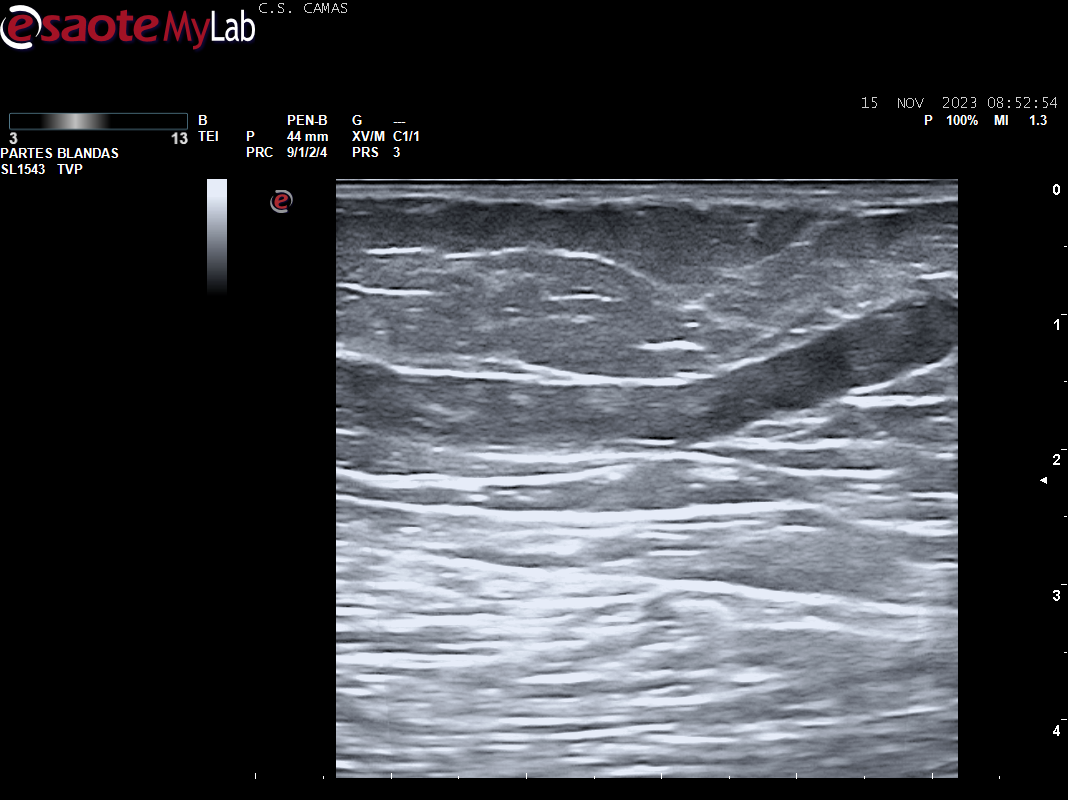

Ecografia vascular cara interna del muslo izq: Trombosis de todo el recorrido de la safena izq con dolor al paso de la sonda por colaterales inferiores que colapsan. Presenta además en zona del cayado de la safena imagen heterogenea sin apreciar la llegada de la safena a la femoral común compatible con arrancamiento de la misma.

Trombosis de todo el recorrido de la safena interna izquierda con tromboflebitis de las colaterales inferiores que concuerda con el diagnóstico hospitalario.